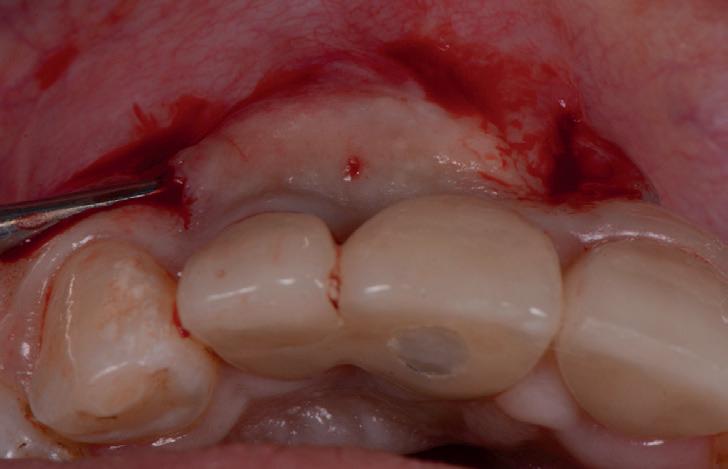

RECONSTITUIREA țesuturilor moi periimplantare. Scopul acestui raport de caz este de a demonstra procedurile chirurgicale utilizate pentru corectarea unui defect al țesuturilor moi periimplantare folosind țesutul moale interdentar în combinație cu tuberozitatea ca locație donatoare de țesut conjunctiv, utilizând o abordare prin tunelizare într-o zonă estetică.

Defectele intraosoase rezultate din periimplantită tind să fie circumferențiale și să aibă o componentă bacteriană din cauza igienei orale insuficiente, a unei margini coronare defectuoase și/sau a prezenței subgingivale a cimentului. Pentru ca tratamentul regenerativ să aibă succes, trebuie abordați factorii cauzali. Îmbunătățirea igienei orale prin utilizarea aței dentare, restabilirea marginilor sănătoase ale coroanei și îndepărtarea cimentului subgingival sau înlocuirea restaurării cimentate cu una înșurubată ori de câte ori este posibil sunt componente importante ale tratării periimplantitei. Dacă este lăsată netratată, periimplantita poate provoca pierderi osoase extinse și în cele din urmă posibila pierdere a implantului.

Pentru un rezultat regenerativ de succes, biofilmul microbian trebuie îndepărtat de pe suprafața implantului. Pentru aceasta au fost folosite diferite tehnici, inclusiv metode chimice sau mecanice, cum ar fi debridarea cu perii, ultrasunete și antiseptice (peroxid de hidrogen sau clorhexidină) și lasere, cum ar fi Er:Cr:YSGG (erbiu, crom:itriu, scandiu, galiu, garnet). Nu există niciun studiu care să demonstreze o metodă superioară pentru eliminarea biofilmului.